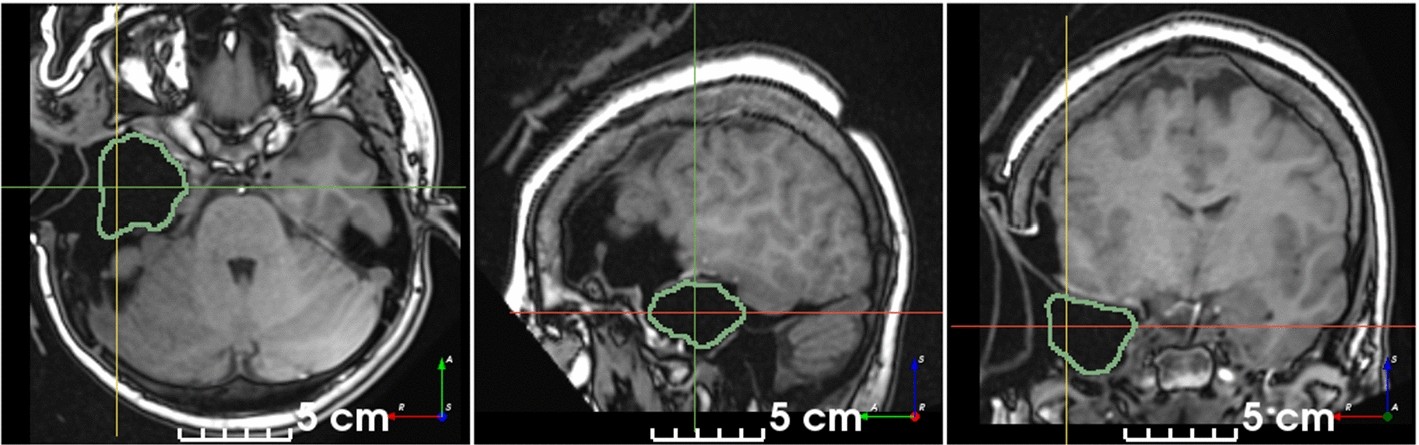

## RESSEG: segmentation of postoperative brain cavities on 3D MRI using deep learning

This is the code for [Pérez-García et al., 2021, *A self-supervised learning strategy for postoperative brain cavity segmentation simulating resections* - International Journal of Computer Assisted Radiology and

Surgery (IJCARS)](https://doi.org/10.1007/s11548-021-02420-2).